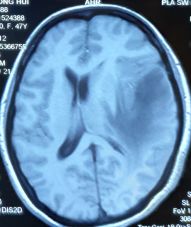

一个月前,47岁的张大姐不幸遇上车祸,在当地医院进行右胫骨上段骨折切开复位内固定术。住院期间,头颅MRI检查提示左颞叶占位。骨折好转出院后,为进一步检查脑袋里面的问题,张阿姨来到重庆主城,在外院行头颅MRI 检查提示"左侧颞部占位,考虑偏恶性肿瘤性病变,脑膜瘤?血管外皮细胞瘤?"

肿瘤周围水肿明显

中线移位